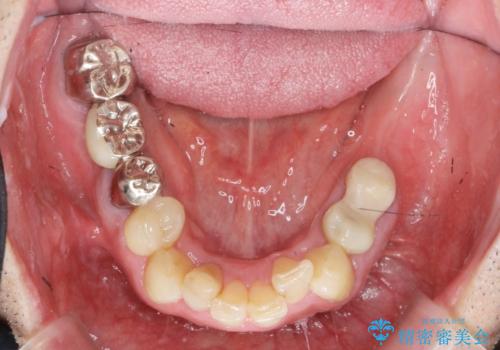

- 「少しずつ色々な箇所が悪くなり、歯医者に通い続けている。全ての歯を長持ちするような状態にできるような治療を受けたい。」、と全顎・総合的な治療を希望され来院されました。

根管治療・矯正治療・歯周外科・セラミック補綴を含む様々な治療オプションを駆使し、長期間良好な状態に保てるような治療計画を立案します。

矯正治療を絡めた総合的な治療をお行なったことで、理想的な咬合関係を確立し安定した噛み合わせで仕上げることができました。

また歯周外科を行うことで歯ぐきの腫れを改善し、清掃性を高めています。